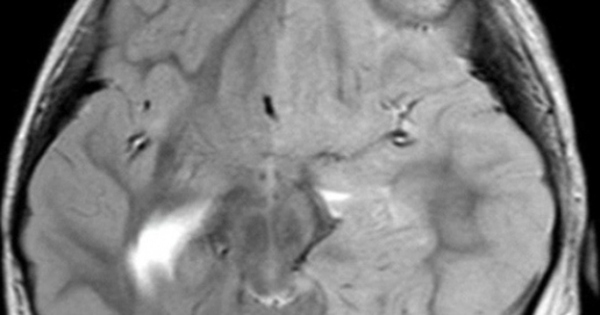

Tại đây, trẻ thể hiện triệu chứng lơ mơ và có cơn co giật lan tràn khắp cơ thể kết hợp với những cơn co giật một nửa người bên phải. Kết quả MRI sọ não cho thấy tổn thương ở bán cầu não trái của bé, trong khi vỏ não bên phải hoàn toàn bình thường. Bác sĩ chẩn đoán bệnh nhi mắc hội chứng Hemiplegia-Hemiconvulsion-Epilepsy (HHE).

Bức ảnh MRI cho thấy những dấu hiệu bất thường ở trẻ bị hội chứng động kinh co giật nửa người (Hình ảnh cung cấp bởi bệnh viện).